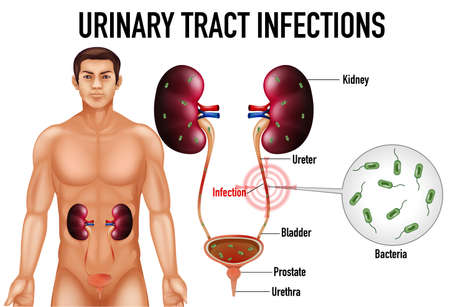

Informative illustration of urinary tract infections illustration